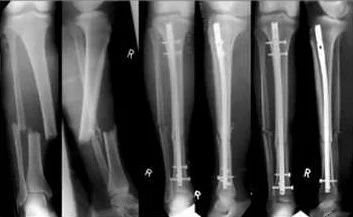

Type of Injury and Fracture Pattern

-

Direct

- Mild force: transverse / Severe force: comminution

- Soft tissue more injured

Indirect

- Pattern of fracture depends on force direction

- Less soft tissue injury

Penetrating

- Missiles

- Low velocity < 300 m/s - damage along the tract

- Comminution

- High velocity: >300m/s - severe comminution

- Comminution with wide soft tissue damage

Displacement

Types of Displacement

- Described as: Position of distal in relation to proximal

- Un-displaced

- Shift

- Sideways

- Shortening

- Distraction

- Angulation

- In all planes

- Rotation